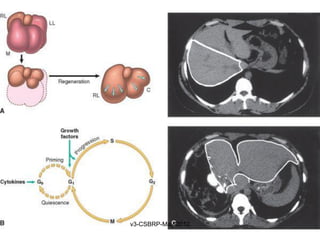

Role of the extracellular

matrix in regeneration

and repair:

Liver regeneration with

restoration of normal

tissue after injury requires

an intact cellular matrix. If

the matrix is damaged the

injury is repaired by

fibrous tissue deposition

and scar formation

LIVER REGENERATION

Hepatocyte proliferation in the regenerating

liver is triggered by the combined actions of

cytokines and polypeptide growth factors

– Priming phase – TNF, IL-6 & C – system

– DNA synthesis – HGF, TGFα, and HB-EGF

– Adjuvants - Norepinephrine, serotonin, insulin,

thyroxin and growth hormone

• Individual hepatocytes replicate once or twice

during regeneration and then return to

quiescence

• Growth inhibitors, such as TGF-β and activins,

may be involved in terminating hepatocyte

replication

• Intrahepatic stem or progenitor cells do not play

a role in the compensatory growth that occurs

after partial hepatectomy

• Endothelial cells and other nonparenchymal

cells in the regenerating liver may originate from

bone marrow precursors